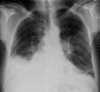

Consolidación con pérdida de volumen y lesiones cavitadas en lóbulo superior derecho. Además, se observa consolidación periférica basal derecha.

Ante una lesión cavitada debes:

• Valorar el grosor de la pared. Una pared gruesa e irregular sugiere neoplasia, mientras que los neumatoceles o quistes broncogénicos tienen paredes finas y más regulares.

• Valorar el contenido. Aparte del nivel hidroaéreo, un hallazgo típico aunque raro es el del aspergiloma, en forma de bola blanca en el interior.